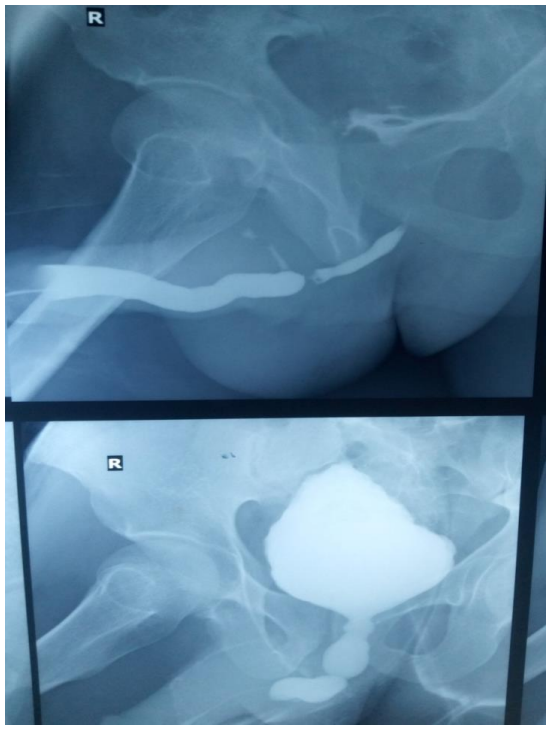

The doctors referred the patient to the radiology department to get scans of his bladder and search for signs of such physical abnormalities. To visualize the bladder in X-ray scans, the radiologists administered an X-ray-sensitive dye through the abdominal catheter. This revealed that the bladder had inflated at its base, leaving a pointy tip.

The diagnosis: This condition is known as a “Christmas tree” or “pinecone” bladder, owing to its appearance.

The X-rays confirmed that urine had been blocked from leaving the organ. Yet a closer inspection of the bladder revealed no issues with the organ itself, such as an obstructing mass or bladder stones. This led the doctors to wonder if an obstruction was located elsewhere.

Further X-ray imaging revealed that the urethra had narrowed significantly about halfway up its length, cutting off urine flow. This condition is called a urethral stricture and has a multitude of causes.